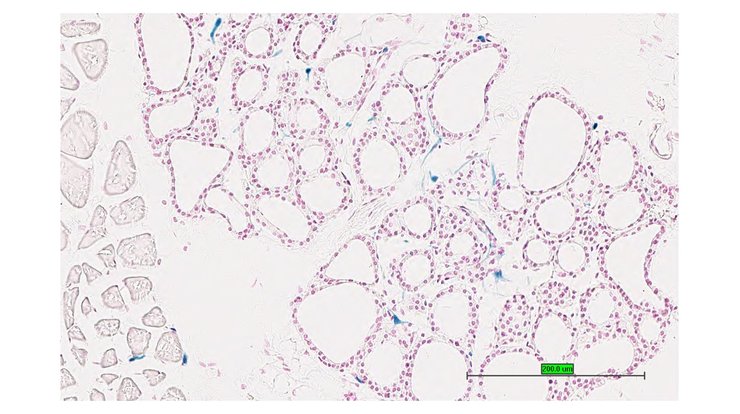

TS28: lung Present UC Davis_1876087

Specimen UC Davis_1876088: postnatal adult; Kcna1tm1.1(KOMP)Vlcg/Kcna1+ (more )

TS28: lung Present UC Davis_1876088

Specimen UC Davis_1876089: postnatal adult; Kcna1tm1.1(KOMP)Vlcg/Kcna1+ (more )

TS28: lung Present UC Davis_1876021

Specimen UC Davis_1876022: postnatal adult; Kcna1tm1.1(KOMP)Vlcg/Kcna1+ (more )

Structure Level Pattern Image Note

TS28: lung Present UC Davis_1876022

Specimen UC Davis_1876023: postnatal adult; Kcna1tm1.1(KOMP)Vlcg/Kcna1+ (more )

TS28: lung Present UC Davis_1876023